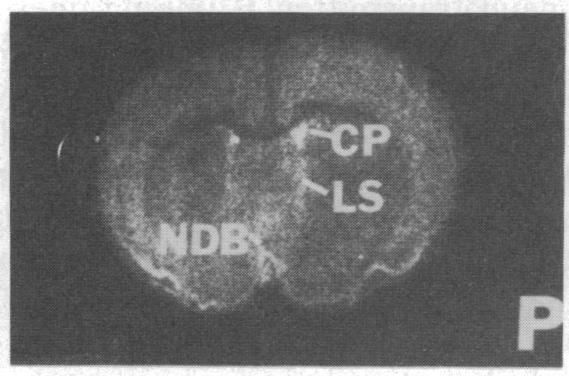

mRNAs for isozymes of phospholipase C (PLC) were localized in rat brain by in situ hybridization with oligonucleotide probes for PLC isozymes I, II, and III of Rhee's group [Suh, P.-G., Ryu, S. H., Moon, K. H., Suh, H. W. & Rhee, S. G. (1988) Proc. Natl. Acad. Sci. USA 85, 5419-5423 and (1988) Cell 54, 161-169], and isozyme I of Bennett and Crooke [Bennett, C. F., Balcarek, J. M., Varrichio, A. & Crooke, S. T. (1988) Nature (London) 334, 268-270], which we designate PLC-A. The isozymes displayed different localizations. PLC-A mRNA was highest in the mitral cell layer of the olfactory bulb, choroid plexus, hippocampus and dentate gyrus, magnocellular hypothalamic nuclei, rostral raphe nuclei, and cerebellar Purkinje cells. PLC-I was highest in the internal granular cell layer of the olfactory bulb, cerebral cortex, caudate, nucleus of the lateral olfactory tract, reticular nucleus of thalamus, hippocampus and dentate gyrus, and granule cell layer of the cerebellum. PLC-II had a more widespread distribution, with relatively high levels in the internal granular layer of the olfactory bulb, hippocampus and dentate gyrus, and cerebellar Purkinje and granule cells. PLC-III label was low throughout the brain. These distributions suggest selective coupling of individual PLC isozymes with particular postsynaptic receptors. PLC-A may be preferentially associated with 5-hydroxytryptamine 1C receptors, vasopressin V1 receptors, and a subtype of glutamate receptors. PLC-I may be linked to muscarinic m1 and m3 receptors as well as other receptors. The distribution of PLC-II mRNA resembles that of src protooncogene, with which it displays sequence homology.

通过与Rhee研究组的磷脂酶C(PLC)同工酶I、II和III的寡核苷酸探针[Suh, P.-G., Ryu, S. H., Moon, K. H., Suh, H. W. & Rhee, S. G. (1988) 《美国国家科学院院刊》85, 5419 - 5423及(1988) 《细胞》54, 161 - 169]以及Bennett和Crooke的同工酶I [Bennett, C. F., Balcarek, J. M., Varrichio, A. & Crooke, S. T. (1988) 《自然》(伦敦)334, 268 - 270]进行原位杂交,将PLC同工酶的信使核糖核酸(mRNAs)定位在大鼠脑中,我们将其命名为PLC-A。这些同工酶表现出不同的定位。PLC-A信使核糖核酸在嗅球的二尖瓣细胞层、脉络丛、海马体和齿状回、下丘脑大细胞神经核、延髓头端缝际核以及小脑浦肯野细胞中含量最高。PLC-I在嗅球的内颗粒细胞层、大脑皮层、尾状核、外侧嗅束核、丘脑网状核、海马体和齿状回以及小脑颗粒细胞层中含量最高。PLC-II分布更为广泛,在嗅球的内颗粒层、海马体和齿状回以及小脑浦肯野细胞和颗粒细胞中含量相对较高。整个大脑中PLC-III的标记物含量较低。这些分布表明各个PLC同工酶与特定的突触后受体存在选择性偶联。PLC-A可能优先与5-羟色胺1C受体、血管加压素V1受体以及谷氨酸受体的一个亚型相关联。PLC-I可能与毒蕈碱m1和m3受体以及其他受体相联系。PLC-II信使核糖核酸的分布与src原癌基因相似,二者表现出序列同源性。